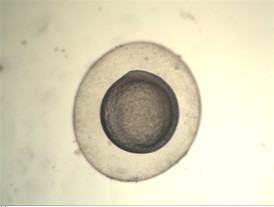

下面是實拍的一些圖片:

體視顯微圖片

體視顯微圖像